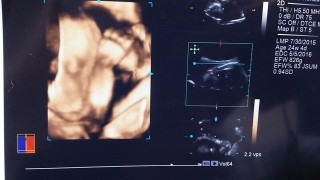

今日、性別が分かりました!男の子でした。大きさは782グラム。胎動も激しいです!今日は炭酸飲んで血液検査?でした。次からは2週間ごとの検診です。